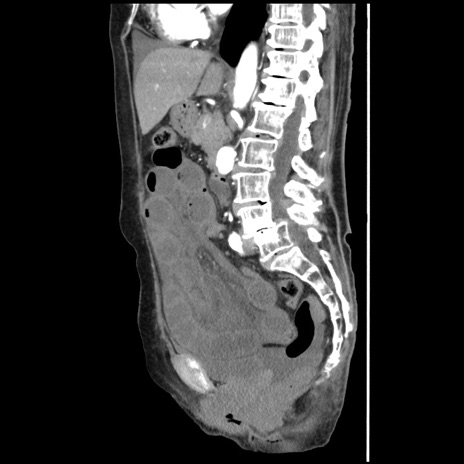

症例1(矢状断像)

【症例】80歳代女性

【主訴】腹痛

【現病歴】8時間前から腹痛あり来院。

【既往歴】糖尿病、脂質異常症、子宮体癌にて子宮全摘術

【身体所見】意識清明・会話良好だが腹痛で苦悶様、全腹部にわたって反跳痛と圧痛あり

【データ】WBC 13600、CRP 0.14、LDH 224、CK 90